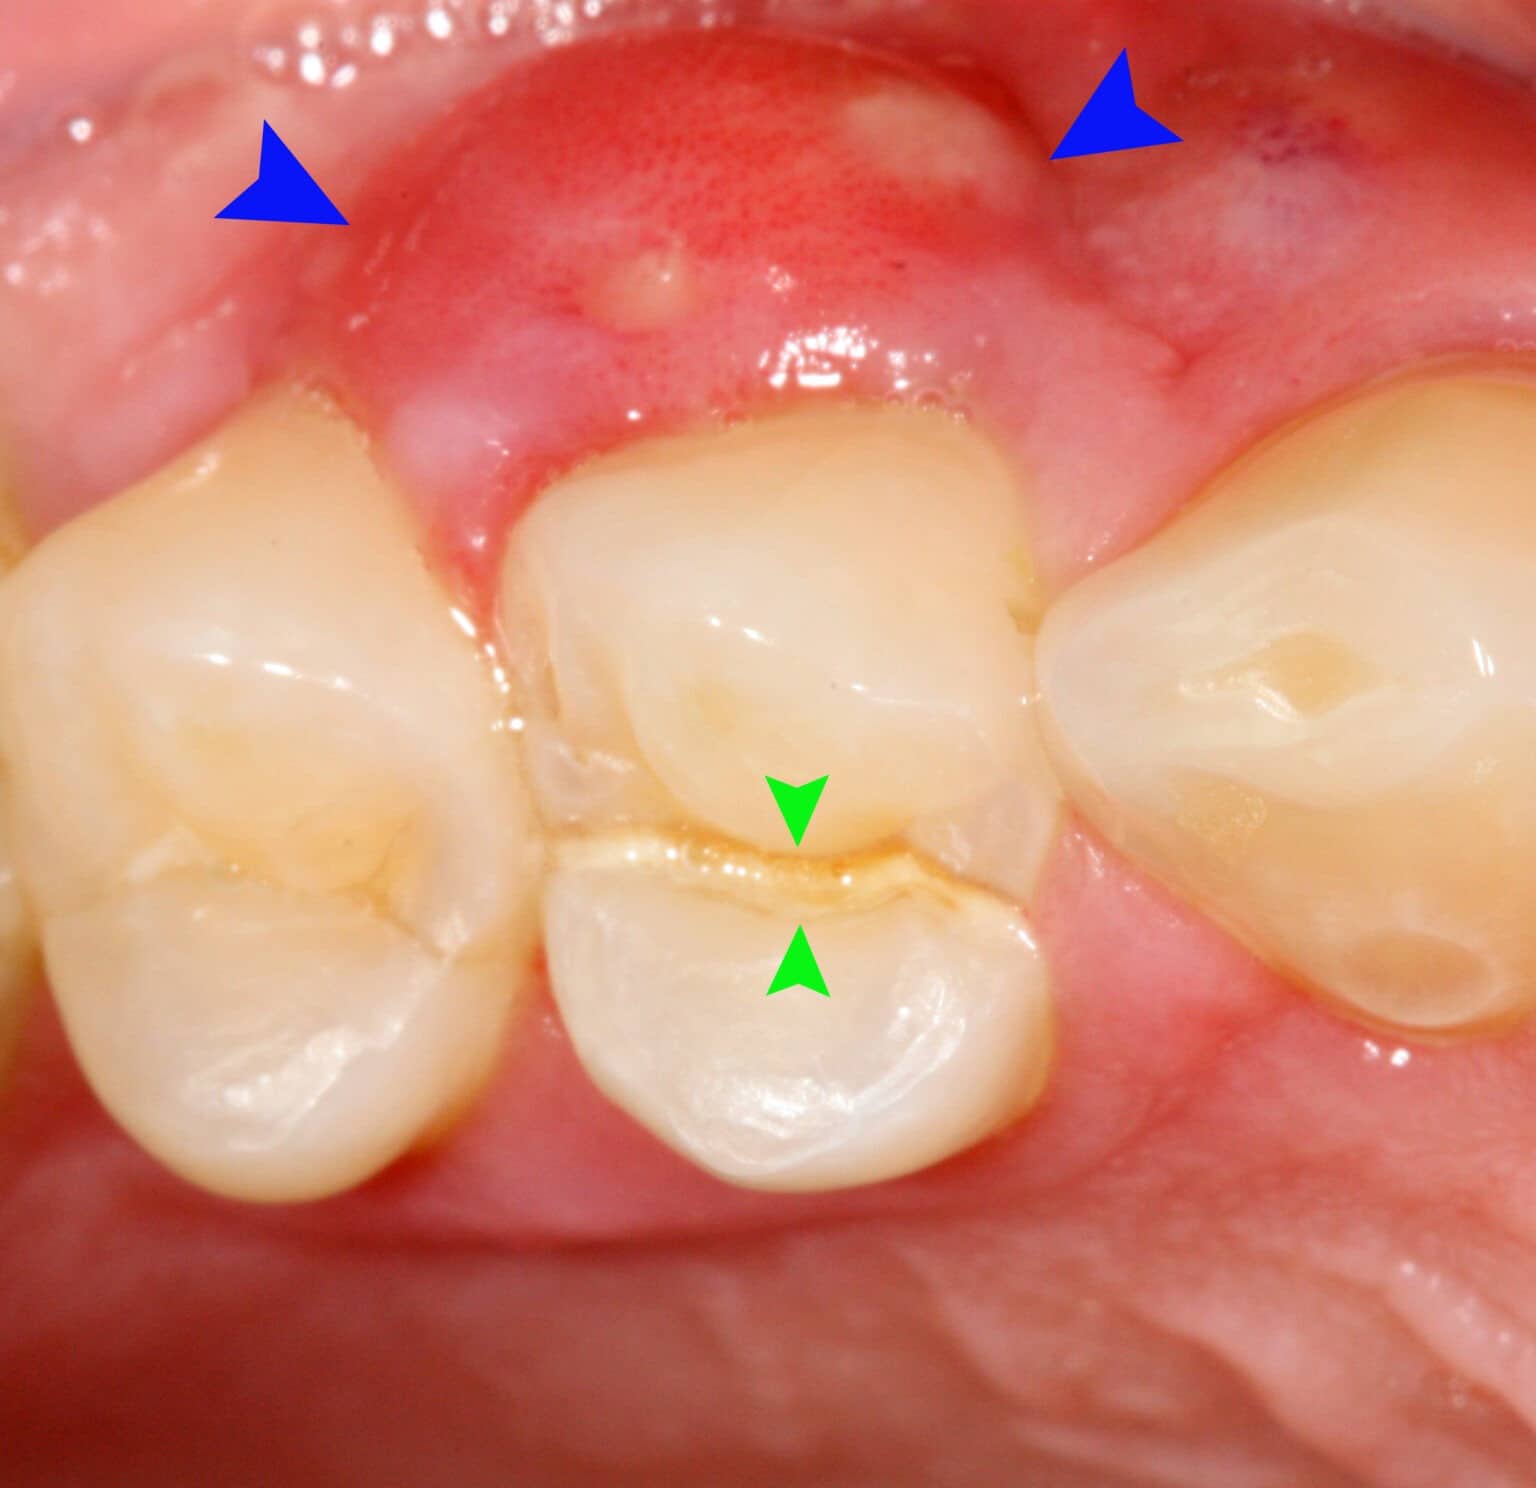

periodontal abscess | DentalDisaster.com

Gum abscess – An infection begins in the pocket of space created …

How You Can Treat The Periodontal Abscess? – Emergency Dentist

Periodontal Abscess | Supernumerary Teeth – Hyperdontia

How to differentiate between Acute Alveolar Abscess and Periodontal Abscess